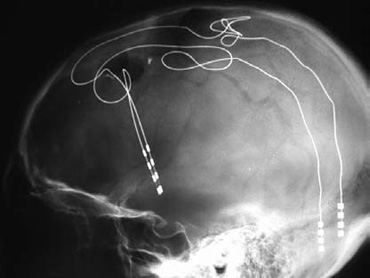

As I write this, I know that tomorrow, I will be caring for a patient in whom a neurosurgical colleague will be placing deep brain stimulators for Parkinsonism. The patient will be somebody who has such severe, medication resistant, brain-mediated joint rigidity and muscle tremors that going out to dine is more-or-less out of the question. Most of the people so afflicted avoid being seen in public at all. He will come to us, willing to undergo brain surgery while wide awake, in the hope that we can alleviate his disability. Sometimes the results are miraculous. Sometimes not.

We do some things to make it better, my favorite being the use of a clear plastic sterile drape that goes straight up from the patient's forehead. We used to use a mayo stand above the patient's face, but this is better; they can gaze up at the OR lights or around at the Stealth surgical navigation computer (more magic) at the foot of the room-less claustrophobic and isolating.